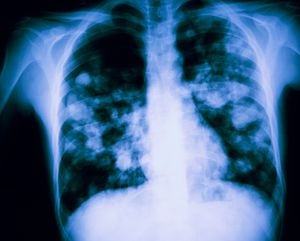

“Un corazón sano es fundamental para proveer el oxígeno y nutrientes que nuestro cuerpo necesita”, destacó la entidad. Por tal razón, dijo que una de las señales de un corazón saludable es que interactúa correctamente con los demás órganos del cuerpo, como el pulmón y el riñón, bombeando la sangre oxigenada de forma efectiva.

Cuando este proceso de conducción no se realiza correctamente, comienzan a manifestarse síntomas que pueden indicar la presencia de enfermedad cardiovascular. Algunos de estos son: